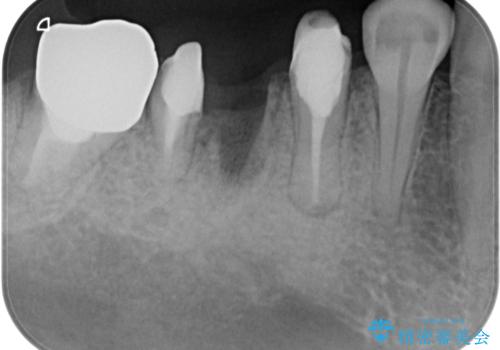

- むし歯を放置したままで、インプラント治療を希望して来院された患者様です。

左右ともにインプラントが必要な状態でした。

左下小臼歯は根管治療で対応する予定でしたが、診断のために歯肉を開いたところ頬側に垂直破折が認められたため、抜歯即時埋入インプラントによる補綴治療を選択することとしました。

右下は大臼歯部の歯は抜歯即時埋入インプラントにて、手前の歯は保存して補綴治療を行うこととしました。